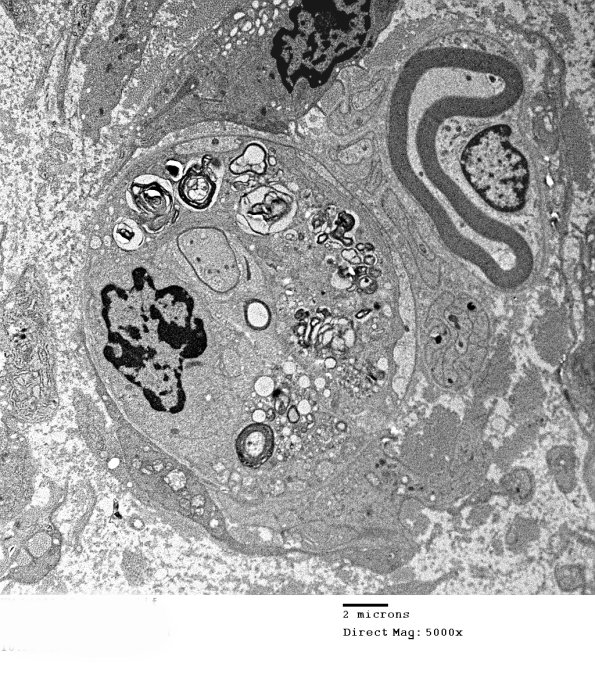

1G1A,B Is this demyelination or remyelination? The higher magnification image shows vesicular myelin in contact with the thin remaining myelin most consistent with late demyelination. (electron micrograph)